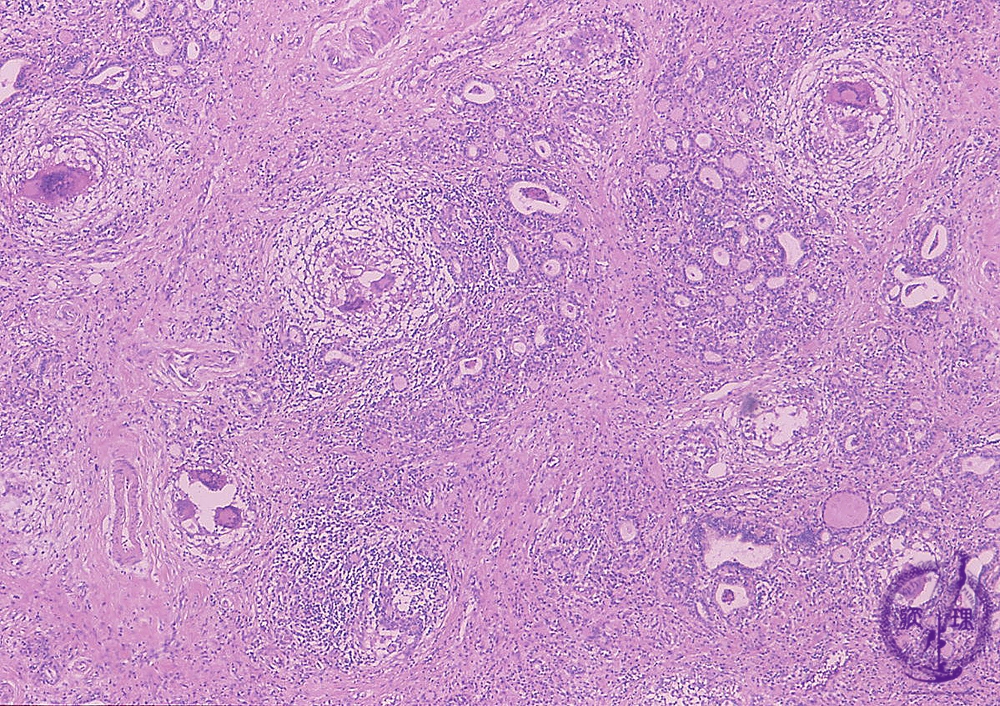

- どうしても診断が付かない場合、炎症の強い部分に甲状腺穿刺細胞診を行い、免疫細胞の多核巨細胞(中等度出現)/類上皮細胞(多数出現)と、好中球(急性炎症の白血球)の浸潤を証明。次項の組織生検(コア生検)で分かるように、多核巨細胞/類上皮細胞は、それ程、数が多くないので、(筆者の経験では)穿刺細胞診をしても検出できない事が多いです。

また、多核巨細胞は結節性橋本病(橋本病結節)や甲状腺乳頭癌でも見つかります。

- 最終手段は組織生検(コア生検)。

甲状腺穿刺細胞診でも亜急性甲状腺炎の診断が付かない場合、あるいは癌性リンパ管炎を否定できない場合、組織生検(コア生検)になります。写真は、病理コア画像[日本病理学会(Japanese Society of Pathology) 教育委員会編集]より引用したものです。